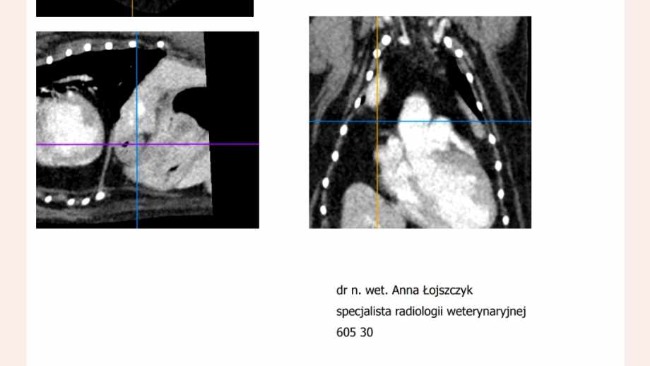

Tomograf komputerowy -1500

Przyszły wyniki TK 😔 Nowotworu nie ma ale .. jest przepuklina przeponowo- otrzewnowa z przemieszczeniem narządów zwłaszcza serca 😭 😭 😭 Jestem już po wstępnej konsultacji z chirurgiem. Operacja na już.😪

Layla jest juz po badaniu . Czuje sie dobrze. Rachunek za tomograf.